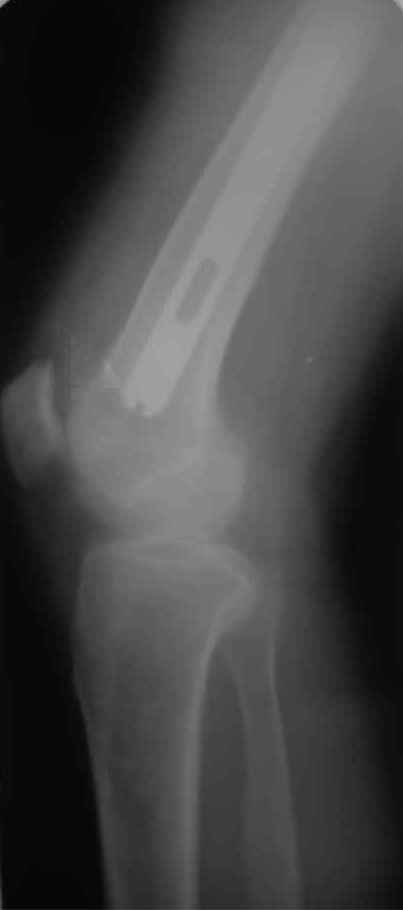

igor 20 Ноябрь 2009, 08:08

новые снимки